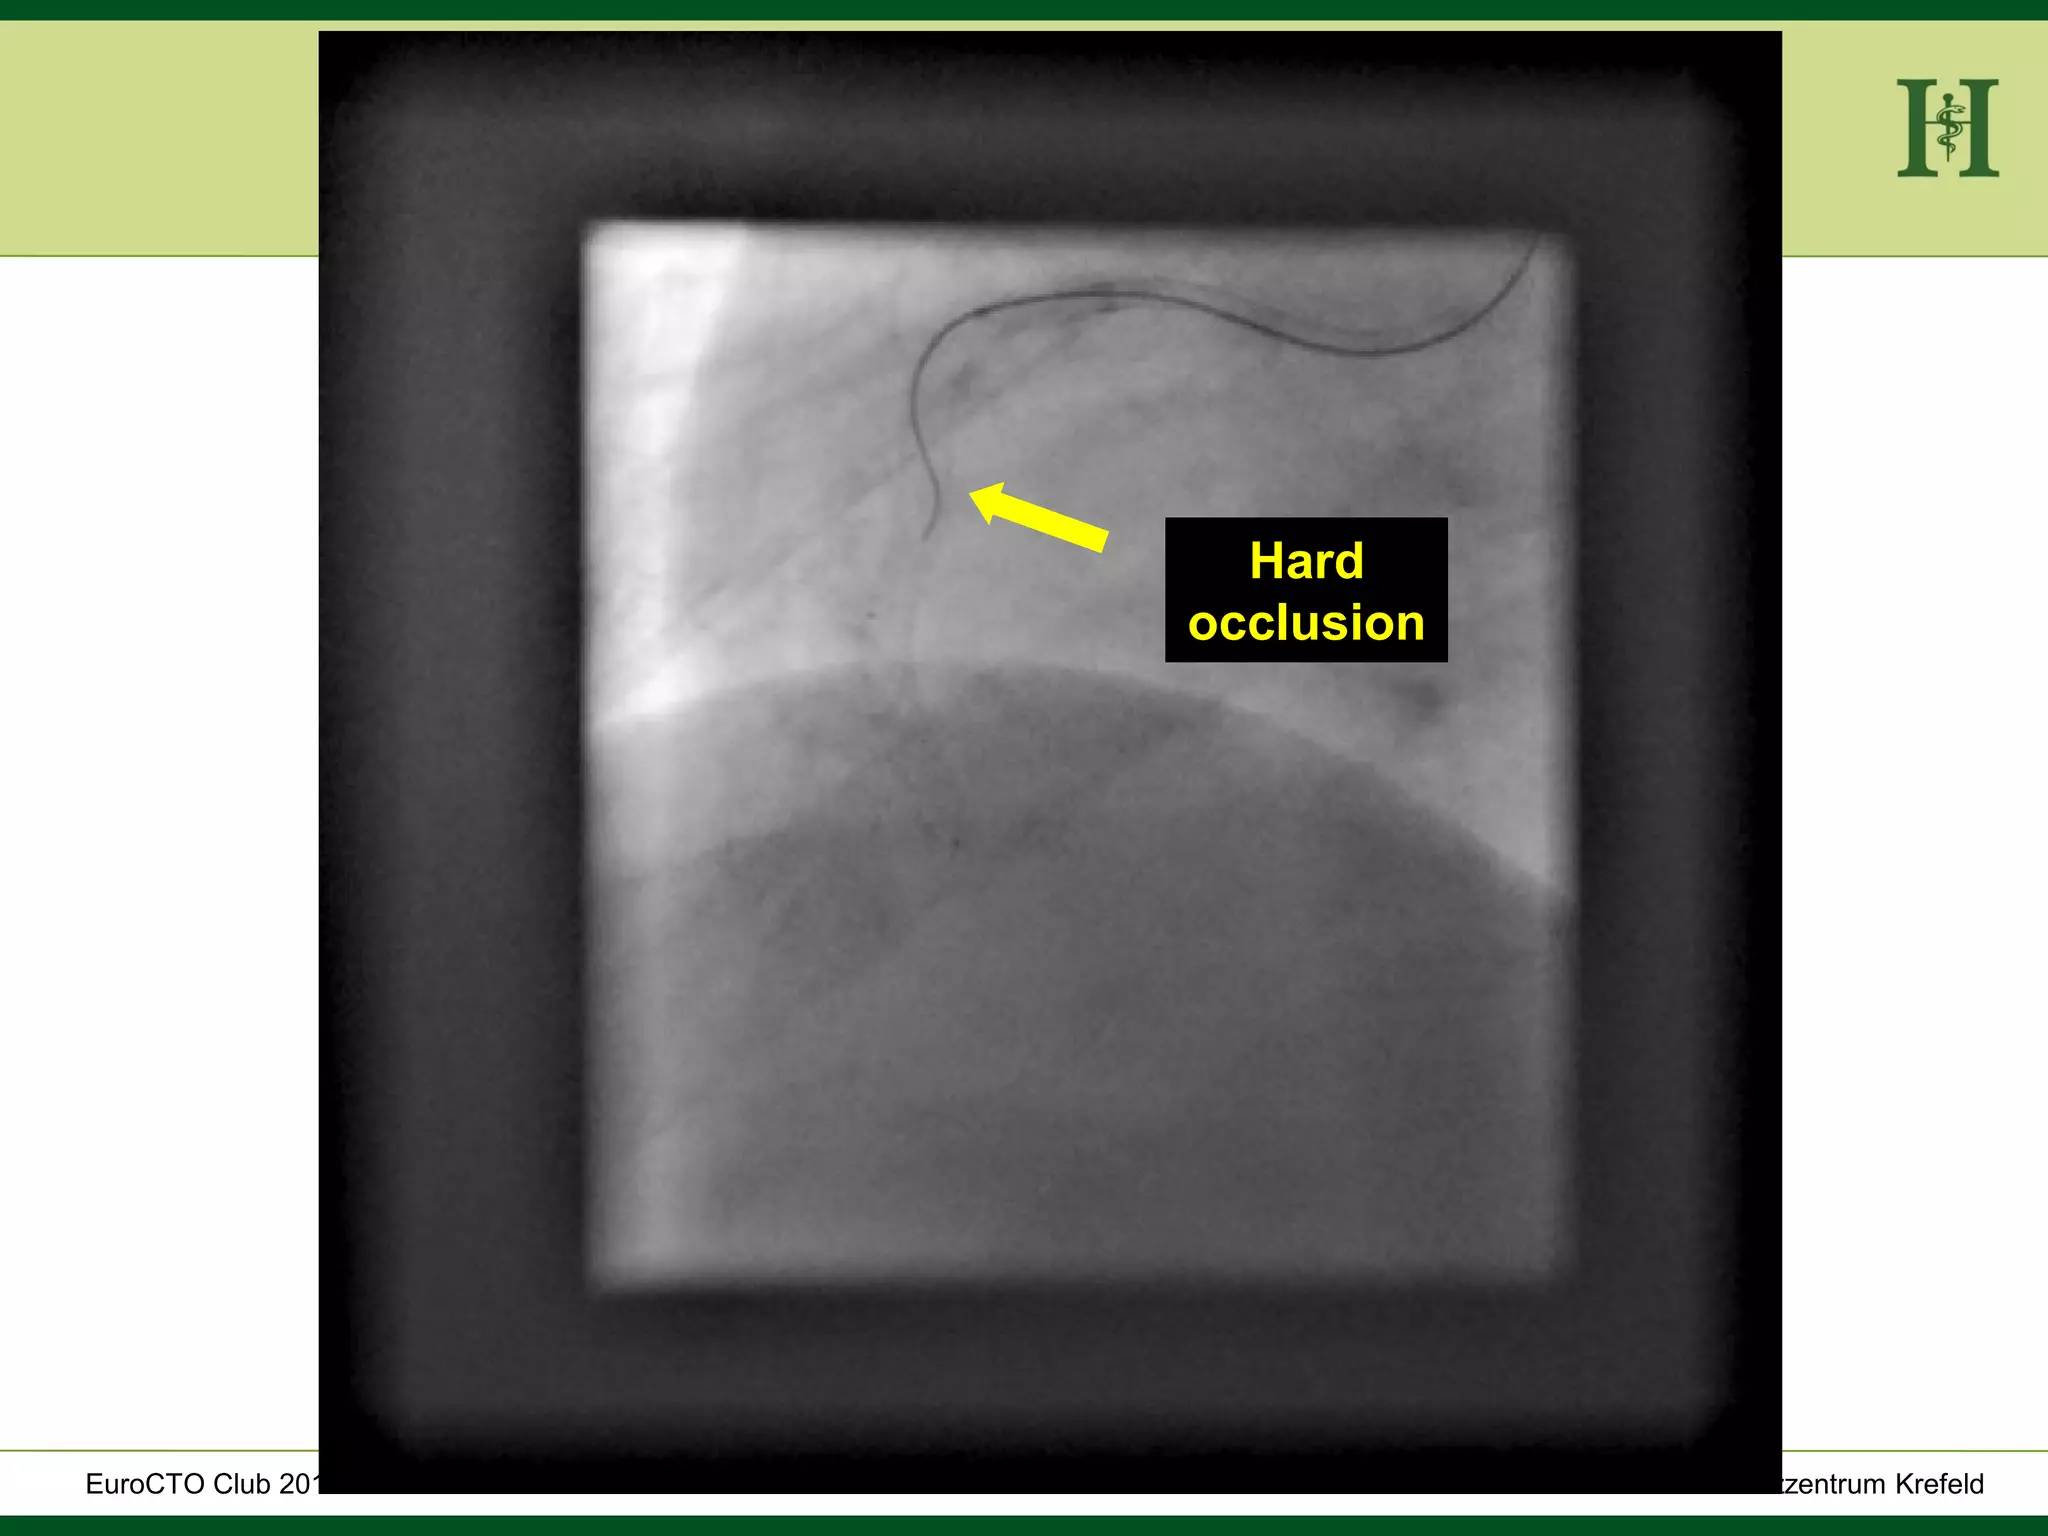

Hard

occlusion

HELIOS Klinikum Wuppertal- HerzzentrumHELIOS Klinikum Wuppertal - Herzzentru A. Bufe - HELIOS Herzzentrum KrefeldEuroCTO Club 2016 Hard occlusion